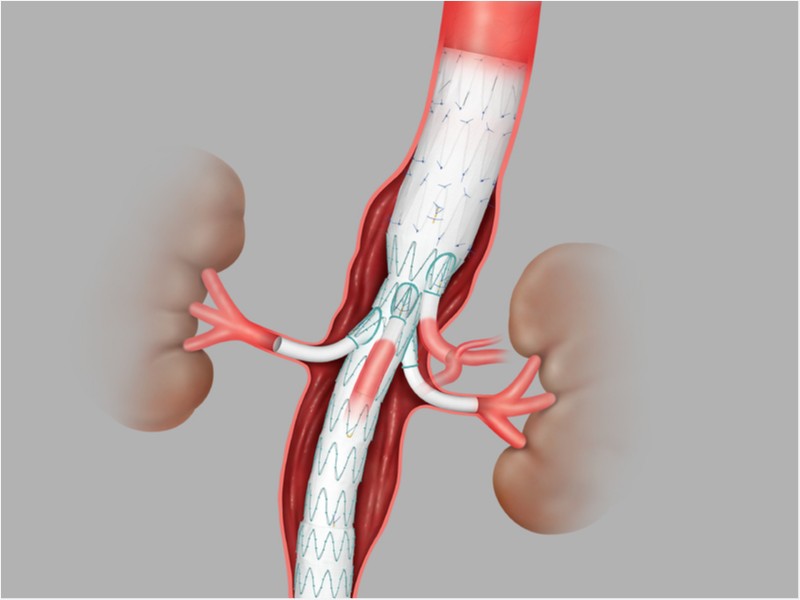

- Endoprótese Endovascular Toracoabdominal Zenith T-BRANCH

Endoprótese Endovascular Toracoabdominal Zenith T-BRANCH

Endoprótese ramificada para aneurisma Toracoabdominal ZENITH® T-BRANCH®, indicada para o tratamento endovascular de pacientes de alto risco com aneurismas Toracoabdominais. Possui Sistema de entrega H&L-B One Shot hidrofílico e aramado de 22Fr.